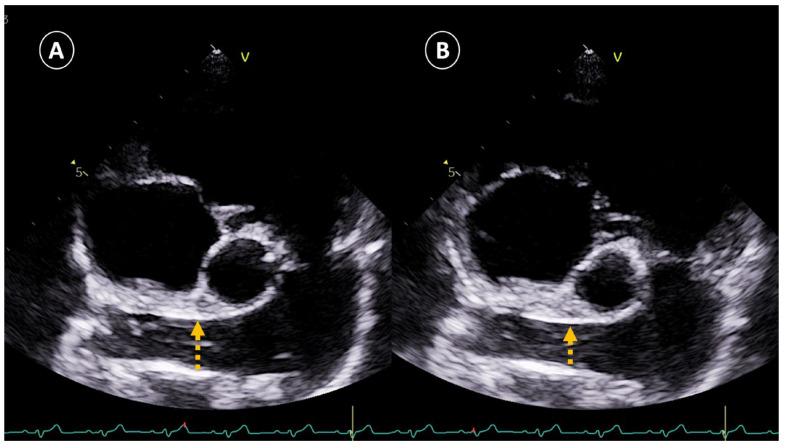

Comparative Echocardiographic Evaluation of Right Pulmonary Artery Dimensions and Right Pulmonary Artery Distensibility Index in Dogs with Heartworm Disease.

Canine cardiopulmonary dirofilariosis or heartworm disease (), is a globally spread vector-borne disease [...].

犬心肺恶丝虫病或心丝虫病(),是一种全球传播的媒介传播疾病[...]